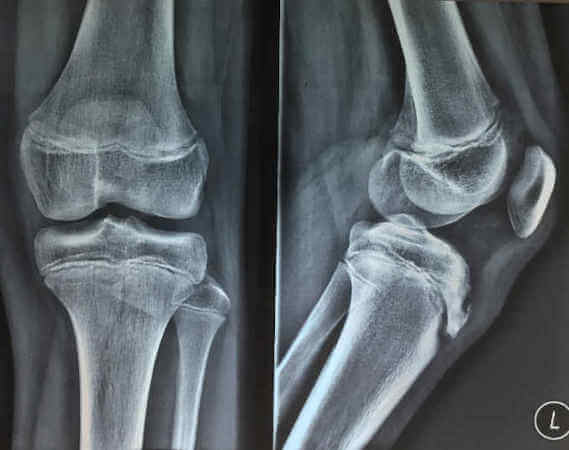

Η διάγνωση γίνεται ακτινολογικά, με ειδικές λήψεις με διακονδύλια προβολή. Τα ακτινολογικά ευρήματα εμφανίζονται σε προχωρημένο στάδιο της νόσου, όταν φανεί του υποχόνδριο κάταγμα ή η απόπτωση του πάσχοντος χόνδρινου τμήματος. Η μαγνητική τομογραφία σε πρώιμο στάδιο ενοχλήσεων αναδεικνύει νωρίτερα την πάθηση, επιτρέποντας την σταδιοποίησή της ανάλογα με τον βαθμό βλάβης (υποχόνδριο οίδημα, νέκρωση, διαχωρισμός με ακέραιο χόνδρο, πλήρης διαχωρισμός).